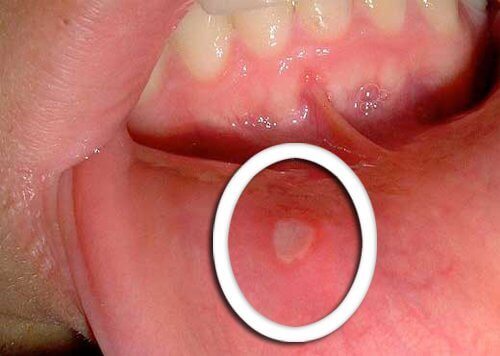

- De tidigaste symptomen på orofaryngeal cancer är små sår som inte läker.

- De är vanligtvis röda eller vita och dyker upp på tungan, tandköttet eller läpparna.

- Var uppmärksam på ovanliga förändringar som inte förbättras på några dagar och tala med din läkare.